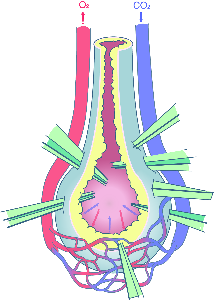

Detailreiche Fotografien aus der medizinischen Praxis ergänzen die Texte; moderne, genaue,

wissenschaftliche Zeichnungen geben Einblick in die Anatomie und die Funktion der Lunge und

anderer Organe.